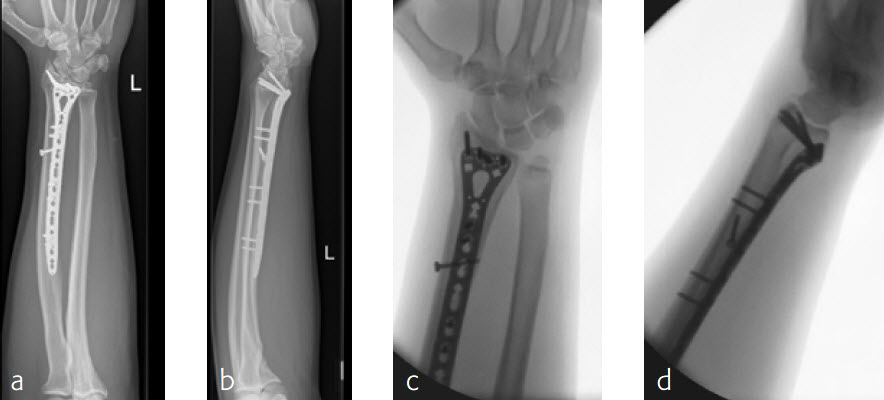

A 26-year-old man suffered a multifragmentary fracture of his left distal radius with extension into the diaphysis (AO23 C3.3) (Fig 2). The VA LCP Extra Long Two-Column plate was used for fixation (Fig 3). After initial immobilization, the plate provided a good postoperative fixation of the fracture.

The fracture showed primary bone healing without callus formation. At the 3-month follow-up, the patient was full weight bearing with excellent clinical function (Fig 4). The radiological follow-up can be technically challenging due to the correct focus of the central ray.